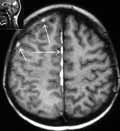

Рис. 3. Подострая стадия субарахноидального кровоизлияния - очаги организации крови (стрелки) в проекции межполушарных и конвекситальных субарахноидальных пространств. (Слева) Т1 режим. (Справа) Т2 режим.